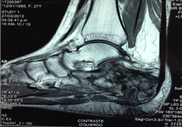

Se realiza una resonancia magnética nuclear (RMN) que mostraba LOE sólido con contornos irregulares localizado en el tejido celular subcutáneo en la región talar izquierda con invasión y erosión ósea del calcáneo izquierdo que posterior a la administración de gadolinio presenta realce heterogéneo de etiología neo-proliferativa (Figura 2).

Figura 2

RMN